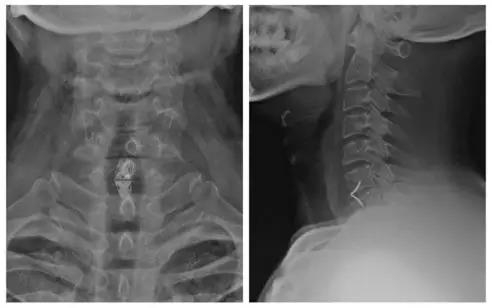

术后X线正侧位片

患者:男,51岁

主诉:双上肢麻木、疼痛一月,加重伴行走不稳3天

诊断:

1.颈椎间盘突出症(C6/7);

2.混合型颈椎病。